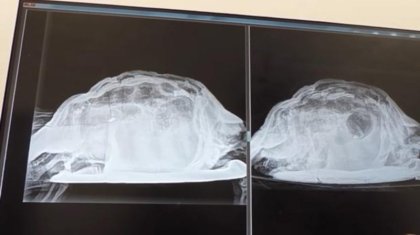

Дәрігерлер британдық қыздың қынабынан тасбақа алып шықты

Испанияда демалып жатқан Ұлыбритания елінің азаматшасы жергілікті ауруханаға ішінің төменгі жағы қатты ауыратынын айтып шағымданған деп жазады КТК тел